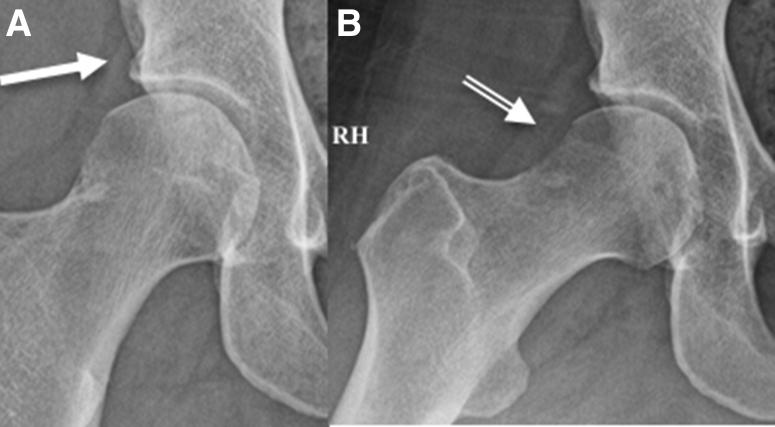

Intraosseous bioplasty (IOBP), has been previously described for arthroscopic-assisted treatment of subchondral bone cysts in the proximal tibia associated with early stages of knee osteoarthritis (OA). This technique entails combining bone marrow aspirate concentrate or concentrated platelet-rich plasma with demineralized bone matrix as a bone substitute before injecting into a subchondral bone defect under fluoroscopic guidance. The principles of IOBP as a procedure that combines core decompression with biologic bone substitute augmentation can be extended to treat subchondral bone marrow lesions such as acetabular and femoral cysts in degenerative hip OA. Intraosseous bioplasty of the hip, in particular the acetabulum, when done using this technique, is a useful alternative that can be beneficial in treating young patients with early hip arthritis to achieve successful outcomes while delaying more invasive procedures. The Technical Note described here presents a step-by-step approach, including tips and pearls for arthroscopic-assisted IOBP with decompression of the subchondral cyst in the acetabulum followed by bone substitute injection under fluoroscopic guidance. We believe this method is a safe and reproducible way to treat subchondral defects in young patients with signs of early osteoarthritis of the hip joint.

摘要

骨内生物成形术(IOBP),此前已被描述用于关节镜辅助治疗与膝关节骨关节炎(OA)早期相关的胫骨近端软骨下骨囊肿。该技术需要在透视引导下将骨髓抽吸浓缩物或富含血小板的浓缩血浆与脱矿骨基质作为骨替代物混合,然后注入软骨下骨缺损处。IOBP作为一种将髓芯减压与生物骨替代物增强相结合的手术方法,其原理可扩展至治疗退行性髋关节OA中的软骨下骨髓病变,如髋臼和股骨囊肿。使用该技术进行髋关节,尤其是髋臼的骨内生物成形术,是一种有用的替代方法,对治疗早期髋关节关节炎的年轻患者有益,可在延迟更具侵入性的手术的同时取得成功结果。此处描述的技术说明介绍了一种逐步方法,包括关节镜辅助IOBP并对髋臼软骨下囊肿进行减压,随后在透视引导下注射骨替代物的技巧和要点。我们认为该方法是治疗有早期髋关节骨关节炎迹象的年轻患者软骨下缺损的一种安全且可重复的方法。